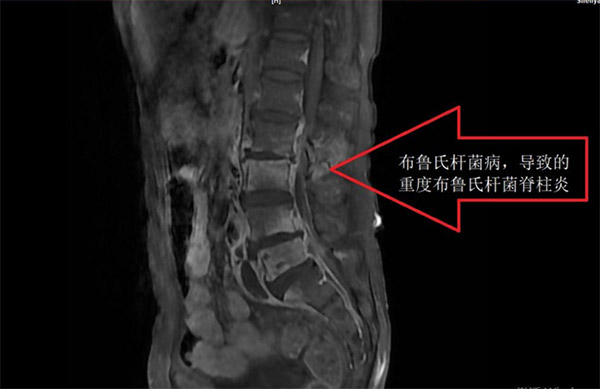

六院骨科主任王天胜介绍,布病脊柱炎患者往往以椎间盘、椎板部位炎症为主,患者表现为强烈的腰痛,有时会伴有大小便失禁。“布病脊柱炎很容易被误诊,有的时候患者单纯的表现为脊柱疼痛,或者关节痛,于是就去骨科看病,而在骨科治疗或手术中才发现布病抗体呈阳性”王天胜说。

老孟入院后,王天胜为老孟进行了胸12椎体-腰5椎体全椎板切除减压、病灶清除、椎弓根螺钉固定术的手术治疗,加固了老孟被病毒侵蚀已经十分脆弱的椎管,排出椎管内脓肿。